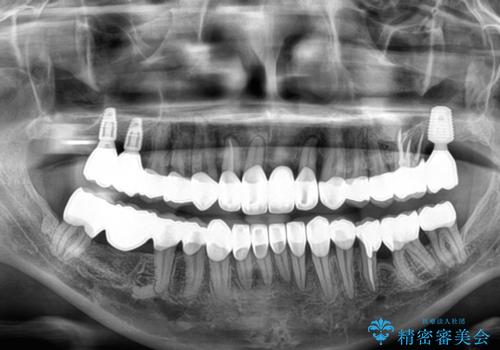

自他共に認める、非常に色白の患者様であったため、黄ばんだ歯の色を白くすることを希望されており、歯周病治療の該当部位に限らず、全顎的にオールセラミッククラウンにて補綴治療を行うこととしました。

多くの外科処置を行ったため、治療期間も長くなり、患者様の負担は非常に大きなものとなりましたが、明るく健康的な口元となり、患者様には大変満足していただけました。